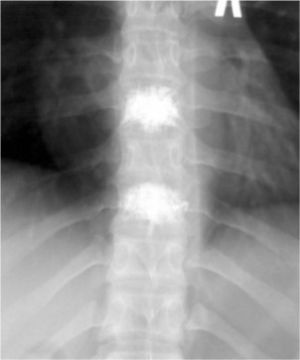

Рис.№4. Рентгенограмма грудного отдела позвоночника в боковой проекции. Определяется удовлетворительное положение костного цемента в телах Th7 и Th9 позвонков.

Рис. №5. Рентгенограмма грудного отдела позвоночника в прямой проекции. Определяется удовлетворительное положение костного цемента в телах Th7 и Th9 позвонков.